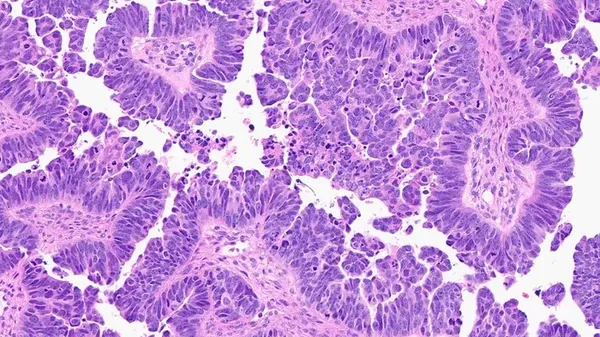

Quando le temperature salgono , il nostro orologio biologico interno è costretto a cambia re ritmo per mantenersi sincronizzato con il suo ciclo di 24 ore : l'attività dei geni coinvolti, infatti, si modifica con accelerazioni e rallentamenti che si …